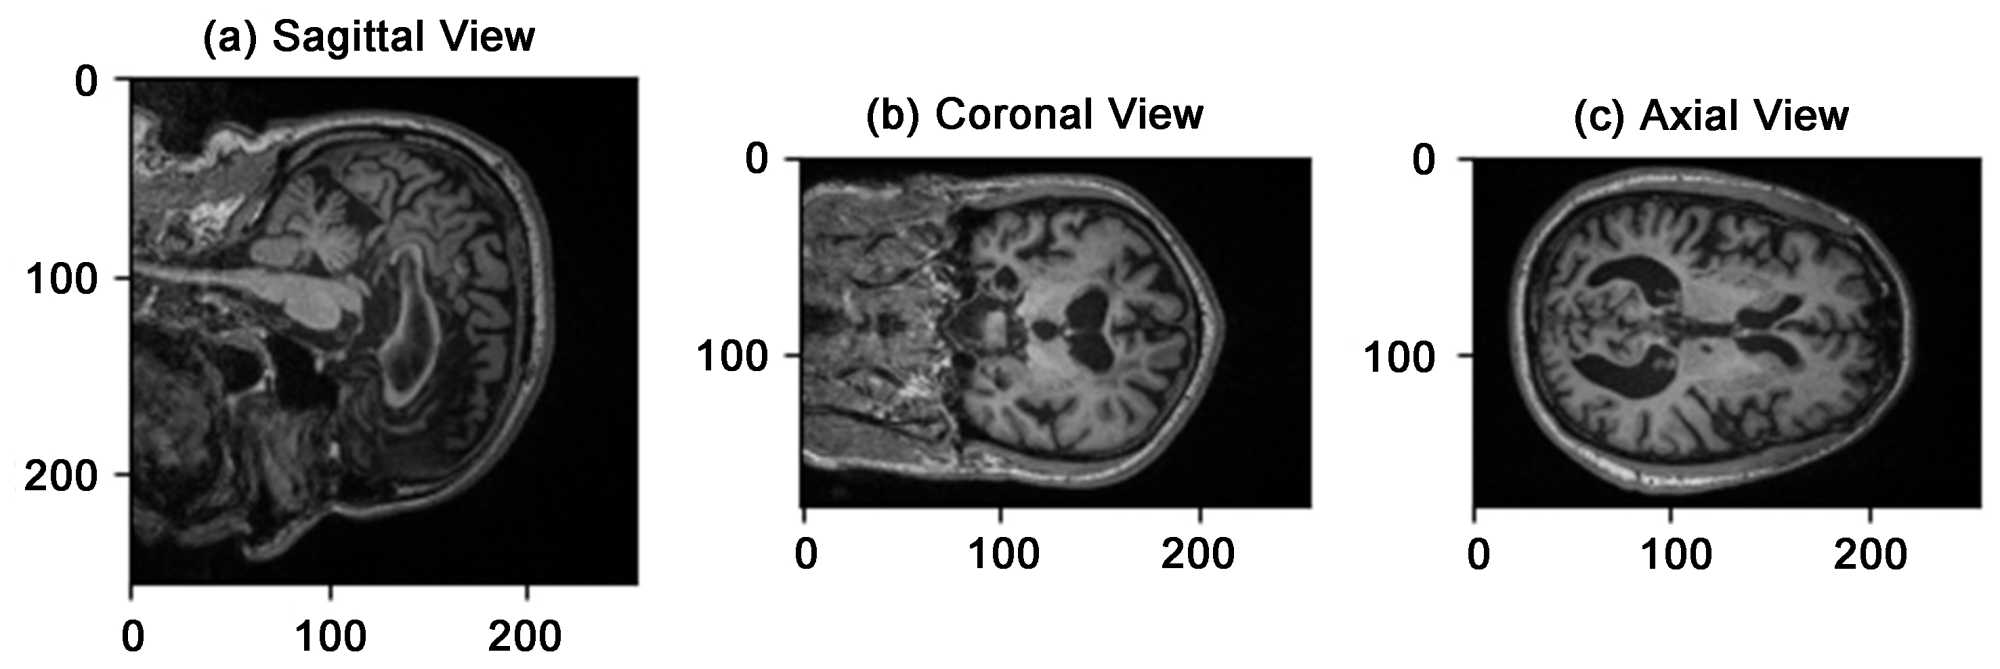

The OASIS-3 dataset is a longitudinal dataset that includes MRI scans of 150 individuals aged 60 - 96 years. The dataset offers a diverse range of brain scans, including those of healthy individuals and those with varying degrees of AD, from mild to severe cases. The availability of longitudinal data allows for tracking disease progression over time. OASIS-3 provides a valuable resource for validating the VIT model. (Figure 1) shows the sagittal, coronal, and axial view of the Oasis-3 dataset once the MRI is sliced across different planes.

Figure 1. Sagittal, coronal, axial view of Oasis-3 Dataset.